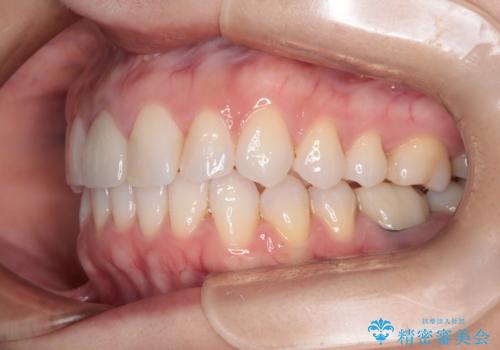

根管治療と並行して矯正を マウスピース治療

- 前歯のガタつき、変色を主訴に来院された患者様です。術前診査のCT撮影にて、変色した前歯の根の先に病巣があることが判明しました。そこで、マウスピースによる矯正治療と、前歯の根管治療、かぶせ物のやり直し治療を並行して行いました。